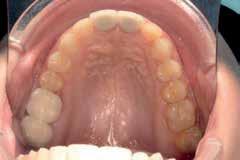

Case 1:

A 24-year-old female presented to the orthodontic clinic with the chief complaint of “Presence of space in the posterior mandibular right region”.

An intra- oral examination revealed the absence of the mandibular right first molar, tilting and oblique inclination of the mandibular second and third molar.

The patient had skeletal and dental class I, a normal overbite an overjet, slight mandibular anterior crowding, rotation of lower right first and second premolars, impaction of upper left and right third molars, and mandibular left third molar.

The patient recalls an extraction that was carried out during childhood but couldn’t specify exactly if it was the mandibular right first molar.

A panoramic x-ray showed the absence of the right first mandibular molar, a 45 degrees inclination of the second and third mandibular right molars, a vertical bone defect at the old extraction site, with a large composite filling on a endodontically treated mandibular left first molar.

Non extraction treatment, with mesial root movement and protraction of the mandibular second and third molars in order to close the residual space, create a solid contact between the mandibular second molar and second premolar without the need for prosthetic dental implant or crown. This option would require longer orthodontic treatment time with extensive follow up visits, however no extra cost is allocated for surgical and prosthetic procedures. (Figures 1 and 2)